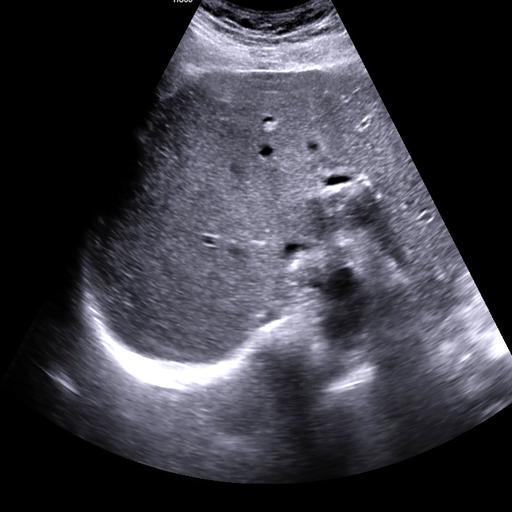

数据样例

结石肾脏样例

- 肾结石在超声图像中主要表现为高回声点,并伴随声学阴影,其形态和位置因结石大小、位置及患者体质不同而变化。